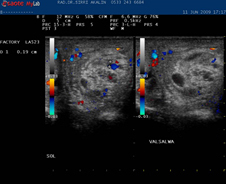

CİHAZ; Esaote Mylab25, portable color doppler